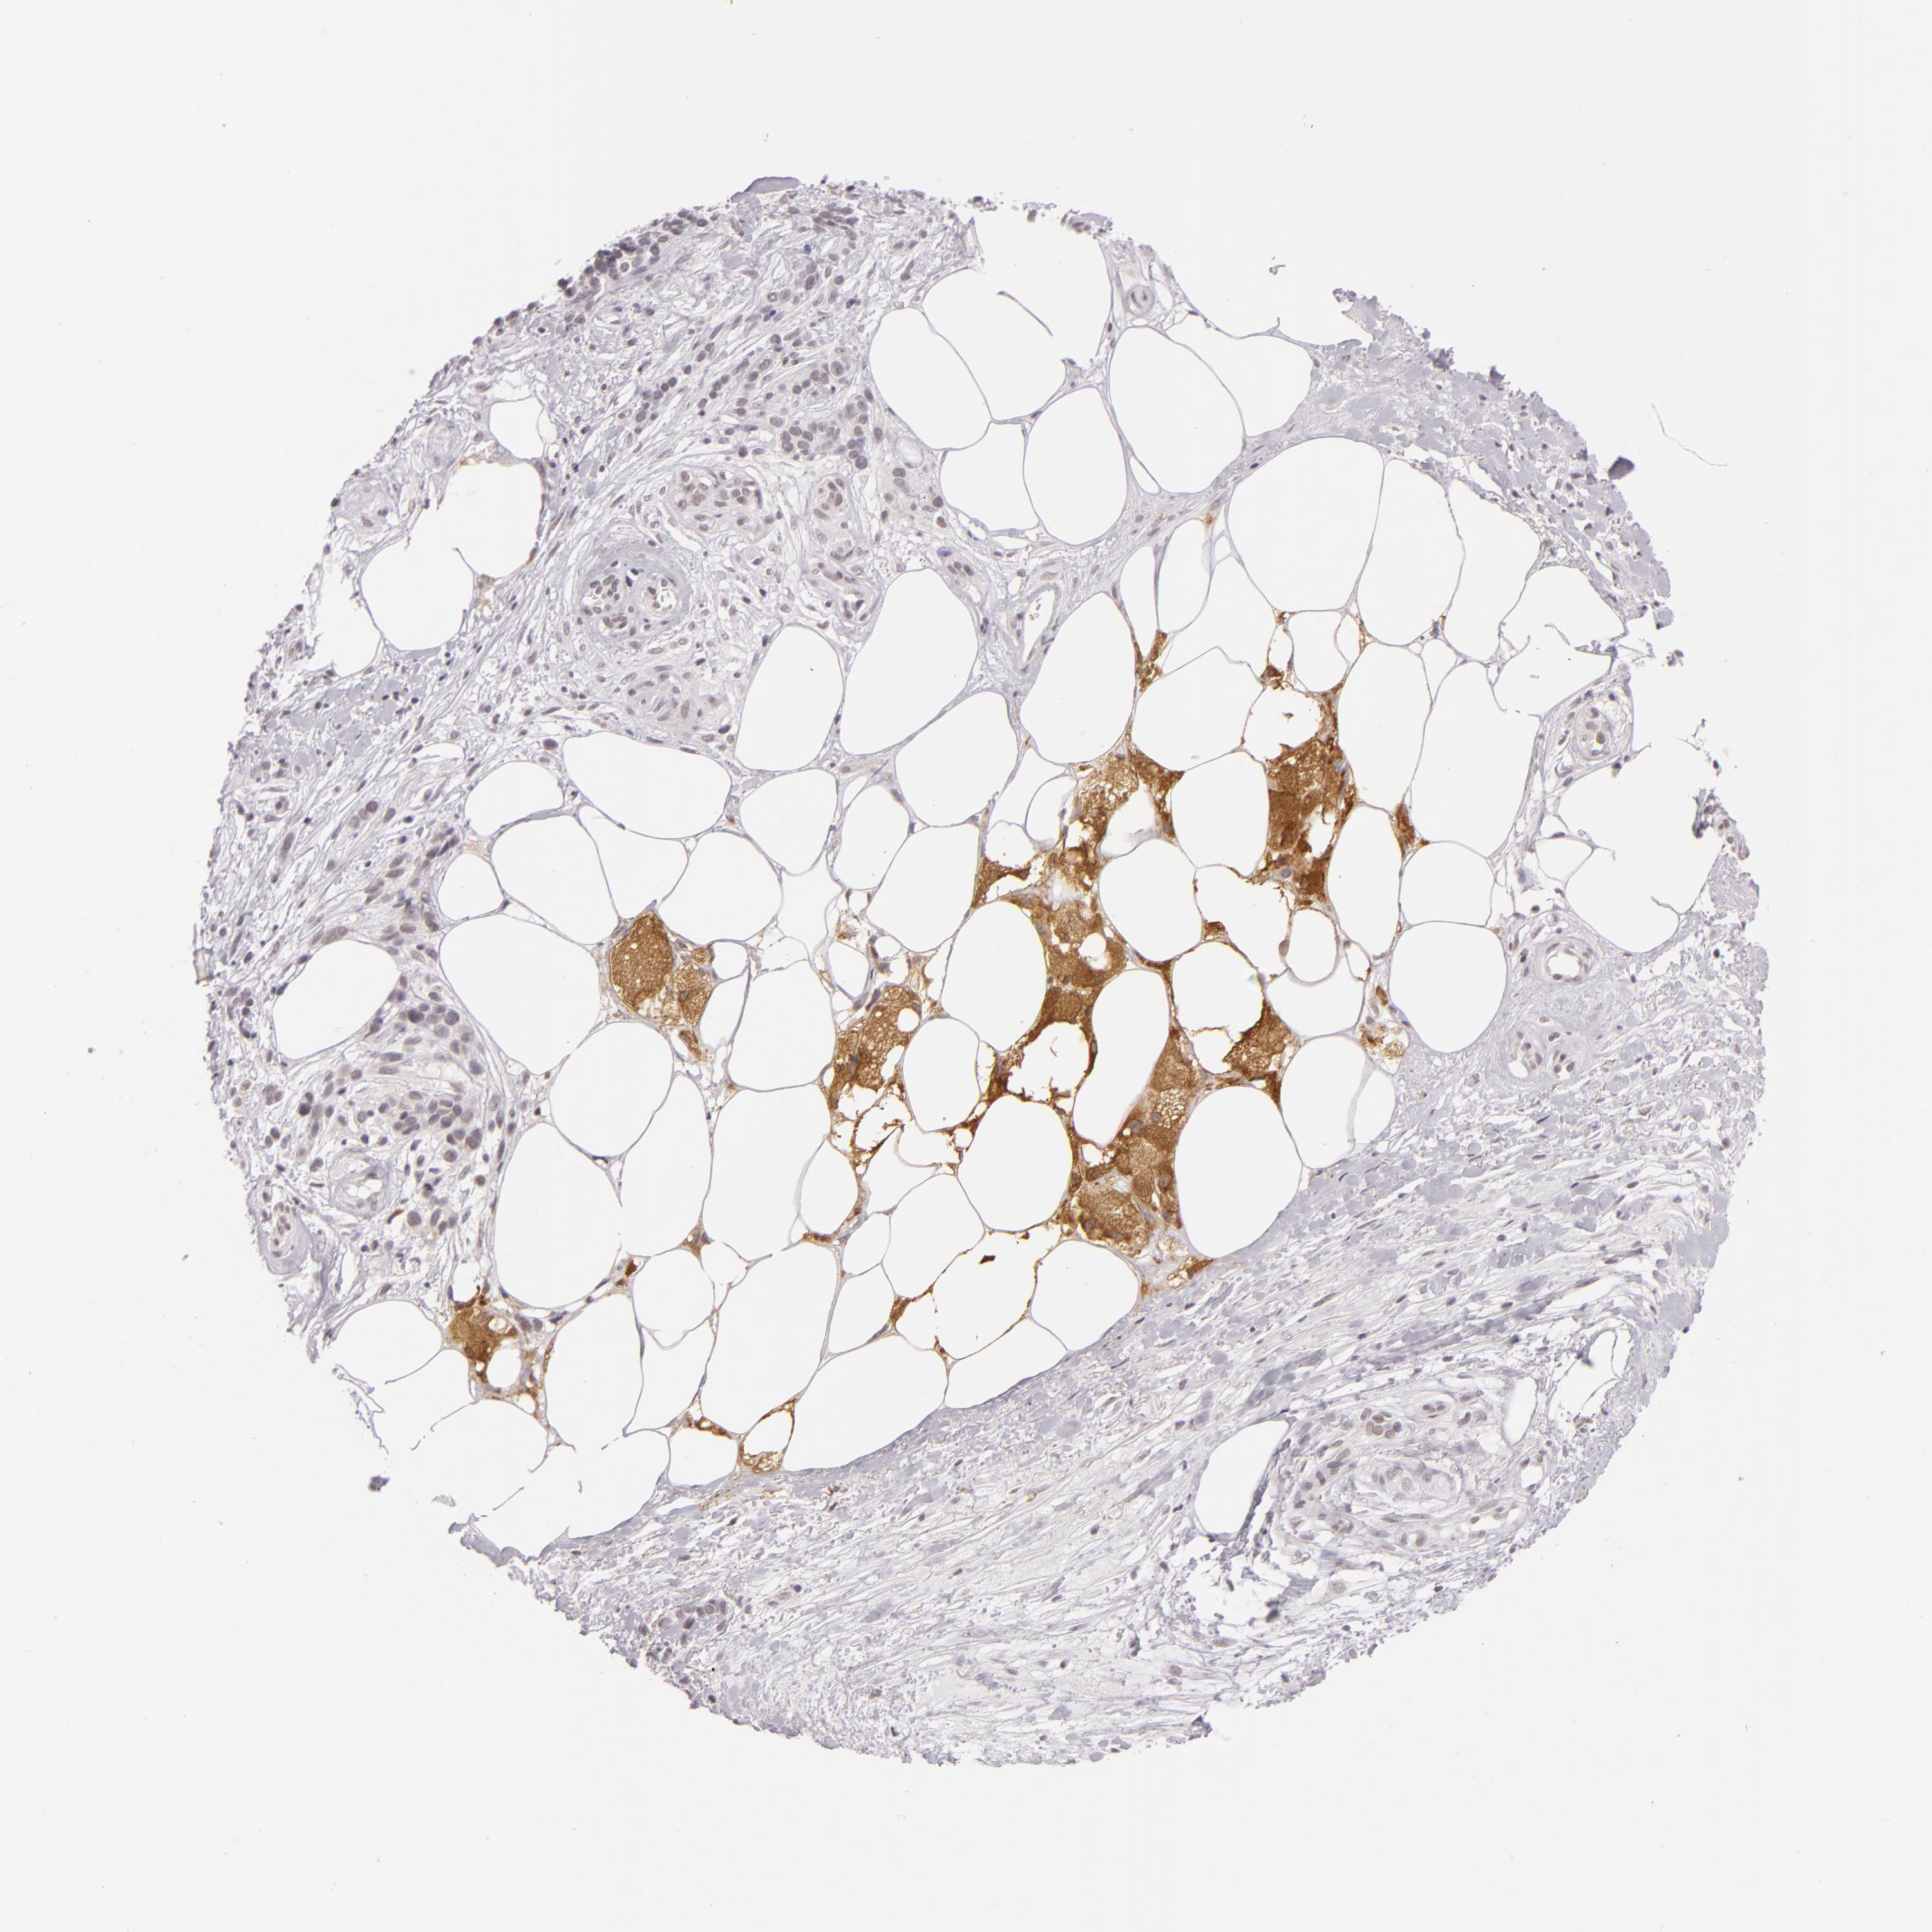

MELANOMA - Protein expressioni

A mouse-over function shows sample information and annotation data. Click on an image to view it in a full screen mode. Samples can be filtered based on level of antibody staining by selecting one or several of the following categories: high, medium, low and not detected. The assay and annotation is described here.

Note that samples used for immunohistochemistry by the Human Protein Atlas do not correspond to samples in the TCGA dataset.

Antibody stainingi

Antibody staining in the annotated cell types in the current human tissue is reported as not detected, low, medium, or high, based on conventional immunohistochemistry profiling in selected tissues. This score is based on the combination of the staining intensity and fraction of stained cells.

Each image is clickable and will lead to virtual microscopy that enables deeper exploration of all samples and also displays staining intensity scores, fraction scores and subcellular localization as well as patient and tissue information for each sample.

Antibody HPA001791

Staining

High

Medium

Low

Not detected

Intensity

Strong

Moderate

Weak

Negative

Quantity

>75%

75%-25%

<25%

None

Location

Nuclear

Cytoplasmic/membranous

Cytoplasmic/membranous,nuclear

Malignant melanoma, NOS